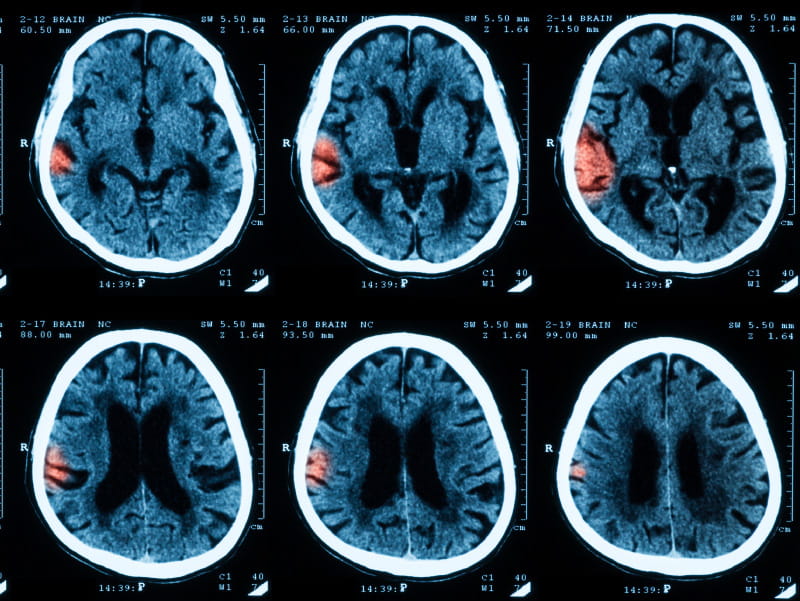

Image of brain scan with stroke.

(Sutthaburawonk/Getty Images)